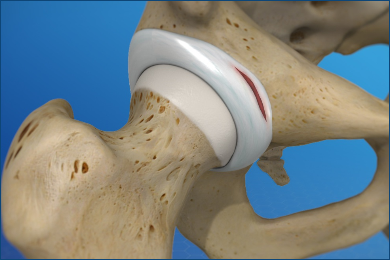

Dr. Kunal Patel, a renowned orthopedic surgeon, offers advanced surgical solutions to treat a variety of hip conditions. With his expertise and state-of-the-art technology, he can help patients restore function and alleviate pain, enabling them to live a more active and fulfilling life.

Whether it's a hip replacement, hip resurfacing, or minimally invasive hip surgery, Dr. Patel provides personalized care and attention to ensure the best possible outcomes for his patients. If you're struggling with hip pain or dysfunction, Dr. Patel can help you find relief and get back to doing the things you love.